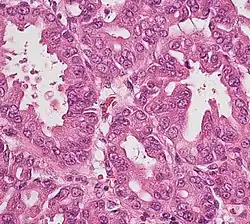

Histopathology

The most common form of pancreatic cancer (adenocarcinoma) is typically characterized by moderately to poorly differentiated glandular structures on microscopic examination. There is typically considerable desmoplasia or formation of a dense fibrous stroma or structural tissue consisting of a range of cell types (including myofibroblasts, macrophages, lymphocytes and mast cells) and deposited material (such as type I collagen and hyaluronic acid). This creates a tumor microenvironment that is short of blood vessels (hypovascular) and so of oxygen (tumor hypoxia).[2] It is thought that this prevents many chemotherapy drugs from reaching the tumor, as one factor making the cancer especially hard to treat.[2][3]

| Cancer type | Relative incidence[11] | Microscopy findings[11] | Micrograph | Immunohistochemistry markers[11] | Genetic alterations[11] |

|---|---|---|---|---|---|

| Pancreatic ductal adenocarcinoma (PDAC) | 90% | Glands and desmoplasia | ![]() |

||